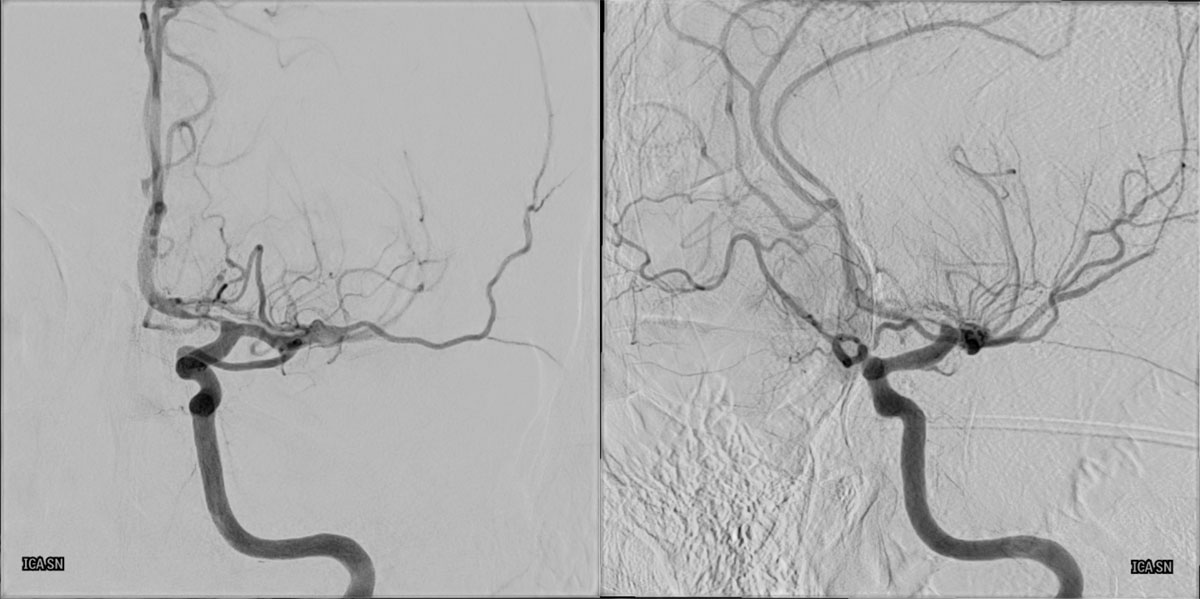

DSA

L - ICA